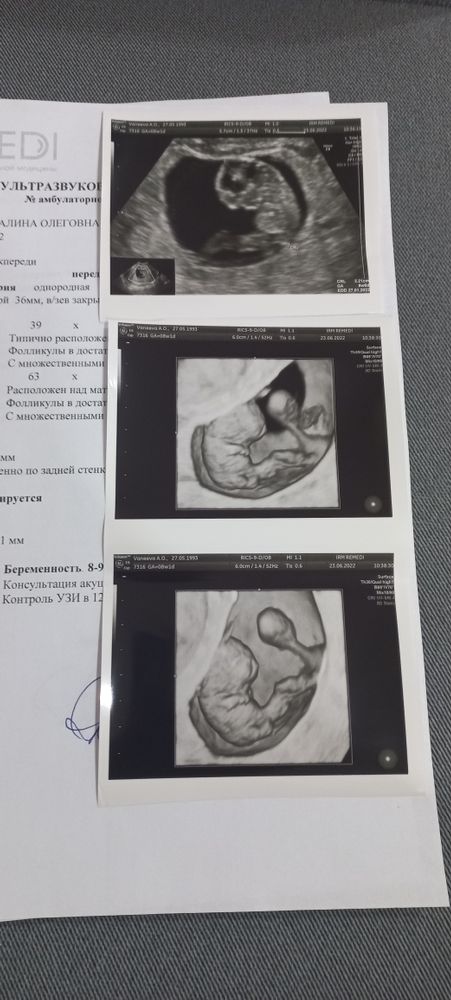

жду мальчика, 10 неделя

Нет ничего прекраснее, чем хороший врач, качественный аппарат и красивые снимки🤩 однако не все платные клиники одинаково нравятся, мой топ- это remedi.Я не устану петь им оды🤣

а что это за чупа-чупс такой большой на снимке напротив малыша?)

Софико, Так выглядит желточный мешочек)

Alina Morissot, да? Как интересно)) А я думала малыш из желточного мешочка получается, простите))) Надеюсь, скоро узнаю все на своем опыте) Снимок просто какое-то чудо нереальное!)

Софико, малыш из плодного яйца, а желточный мешочек, это то, чем малыш питается какое то время, пока не функционирует пуповина)

Alina Morissot, спасибо))) Это значит у крохи там с собой котомочка с едой)))

3D прям сказочка, ни разу не делала, а так хотелось бы)))

Oljha, это вообщеее, как будто какая то параллельная реальность 🤣🤣

Oljha, я вчера ходила на 4-е узи за 11 недель, сначала смотрели обычным режимом потом включили 3 D, это что-то, все видно и пальчики и ушки и глазки и как он двигается и писюн тоже рассмотрели, как-будто сами с мужем в матке сидели 😁 Я как всегда в ступоре тряслась от страха, зато муж все на телефон снимал и улыбался, многие пациенты не только мужа берут а ещё и детей, они тоже в восторге 😍.

Ааааа какие снимки крутые!!! Красота! А какой у вас срок? Я примерно помню, что у нас с вами где-то неделя разницы)) я завтра иду вставать на учёт, а сегодня утром ходила на УЗИ (через неделю после последнего у Ре😁), но чувствую, что до 1 скрининга не дотерплю и пойду ещё 🤤

Екатерина , Ага! Уже на профессинальную фотосессию сводила- к хорошему надо приучать с измальства! Срок 8 нед. 1 д.

Алина,узи просто космос,так четко видно малыша!!Супер!